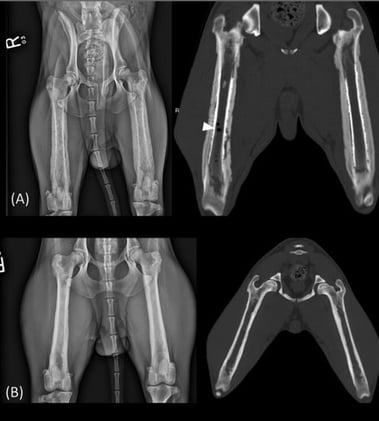

Feline

+2

Apr 26, 2026

•

3 min read